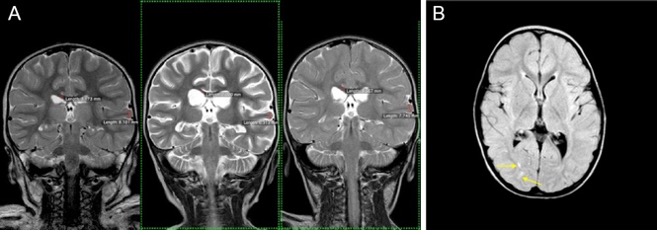

Two-year-old Eden fell in the family pool. She was revived 3 times. Her original prognosis was that she would remain in a vegetative state for the rest of her life. She received HBO from Dr. Harch in New Orleans and has had an amazing recovery!

Note: (A) T2 coronal images at the level of the thalami from left to right at 3, 31, and 162 days post-drowning, showing reversal of white matter and cortical atrophy. Corpus callosum white matter and temporal lobe gray matter calculations embedded: 3.17, 2.00, 3.57 mm, and 8.10, 6.31, and 7.75 mm, at 3, 31, and 162 days.